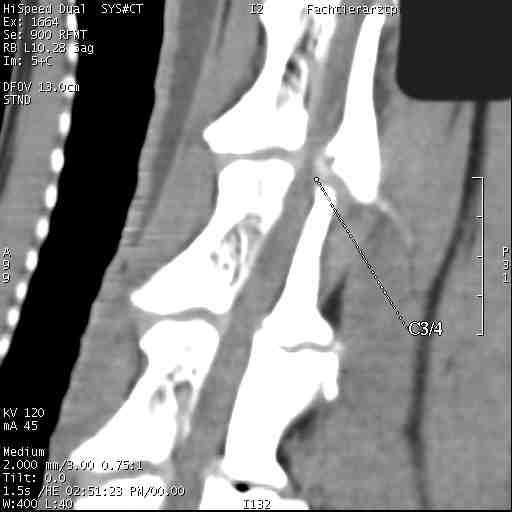

Im folgenden Beispiel sieht man computertomografische Bilder der Halswirbelsäule einer Dogge mit folgender Diagnose: Knöcherne Stensoe C3/4 [= 3./4. Halswirbel], sanduhrförmige Kompression des Myelons auf der Höhe C3/4, Bandscheibenvofall C6/7 [= 6./7. Halswirbel], Myelon mit seitlicher Abweichung nach links : Im Ergebnis eine Halswirbelstenose an den beiden Stellen mit Kompression des Myelons, die zu den Lähmungserscheinungen führt.